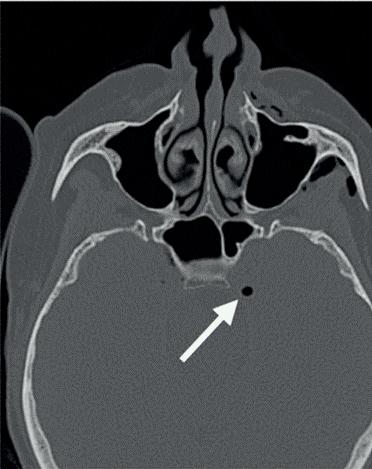

In dit geval heb ik mijn collega die belde voor advies, geadviseerd om contact op te nemen met de implantoloog waar ze mee samenwerkt. De kans dat implantologie op termijn nodig zal zijn, is namelijk heel erg groot. De patiënt kon dezelfde dag nog terecht bij tandarts-implantoloog Tristan Staas. Naast de aanwezige solo is er een CBCT gemaakt (foto 5 en 6). De behandelmogelijkheden zijn hierna uitgebreid besproken.

Er is in deze casus door de implantoloog gekozen om element 21 terug te plaatsen, in de hoop dat het zo lang mogelijk goed blijft gaan. Het stolsel is met een implantaatboor uit de alveole verwijderd en de alveole is iets verruimd. Eigenlijk dezelfde procedure als bij een autotransplantatie. Hierna is het element uitgebreid afgespoeld met fysiologisch zout, teruggeplaatst en aan de spalk bevestigd. Voorheen was,

5. Solo gemaakt meteen na het trauma door de spoeddienst.

6. Screenshot van de CBCT.